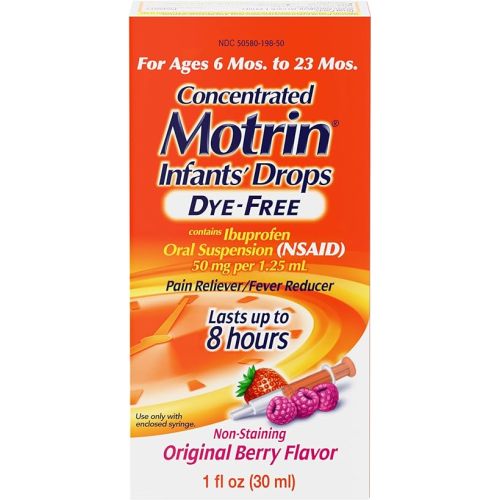

Motrin Infants' Oral Suspension Concentrated Liquid Medicine Drops with Ibuprofen, NSAID Infant Fever Reducer and Pain Reliever for Babies, Dye-Free, Alcohol-Free, Berry Flavor, 1 FL OZ